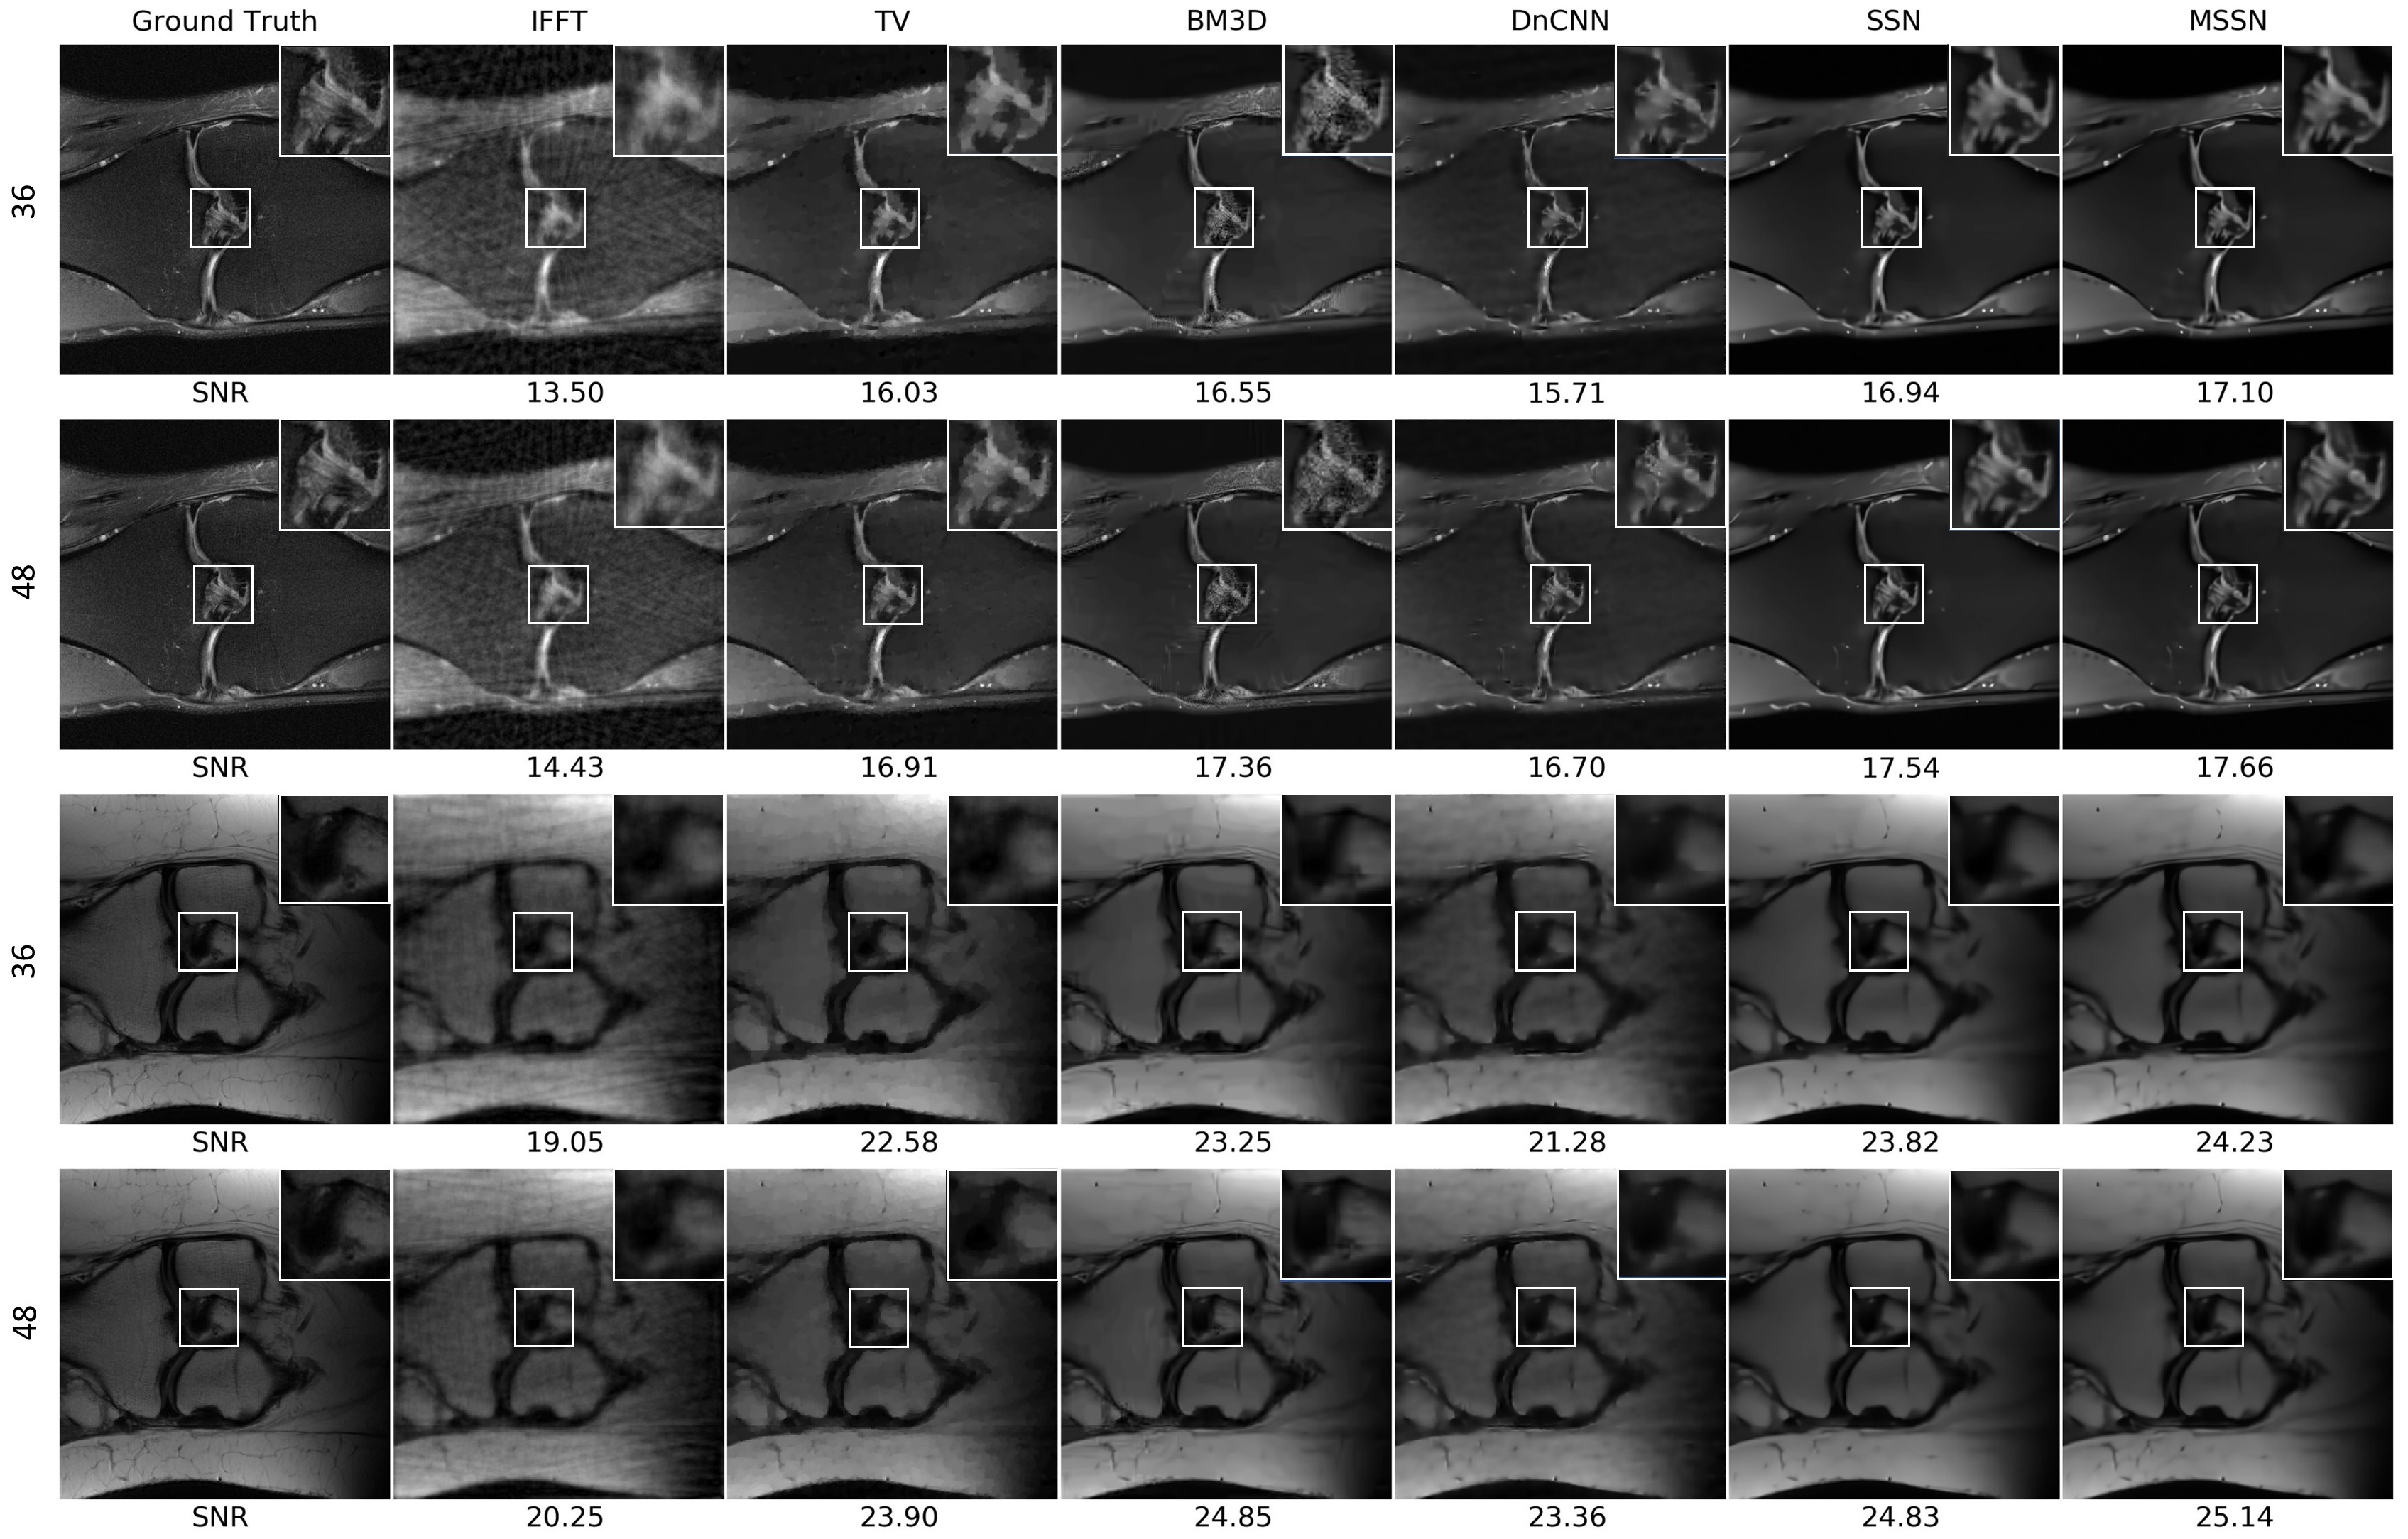

Figure 2 demonstrates the details of the MRI reconstruction. The first two rows are the reconstruction results of no. 58 in fastMRI dataset using 36-lines and 48-lines radial sampling respectively. The last two rows are results of no. 21119. Visual inspection of reconstructed images reveals that proposed denoiser is robust in these two T1, T2-weighted MR images of bones, and artefacts are diminished using SSN or MSSN denoiser compared to conventional denoisers. More crucially, PnP algorithm using MSSN keeps subtle yet important anatomical details and offers more faithful reconstructions that can be recognized in the zoomed-in views.

Figure 2: Illustrations of MRI reconstruction from k𝑘k-space downsampled data (no. 58 and no. 21119 using radial sampling, the first and third rows use 36 lines for sampling and the second and the fourth rows use 48 lines) using different denoisers within PnP. Each reconstruction is labeled with its SNR (dB) value with respect to the ground truth.

The quantitative results in Table 1 show that MSSN outperforms the optimized conventional regularizer TV, BM3D, and DnCNN denoisers. MSSN achieves the highest average SNR of 21.18 dB when using 36-lines k𝑘k-space subsampling and 22.03 dB when using 48 lines. The SSN denoiser is competitive with BM3D without using the mixed multi-head attention. The MSSN denoiser further improves the reconstruction performance compared to SSN, and results in the lowest reconstruction error, even when trained on natural images.